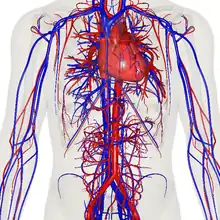

![]() The human circulatory system (simplified). Red indicates oxygenated blood carried in arteries. Blue indicates deoxygenated blood carried in veins. Capillaries join the arteries and veins. | |

In vertebrates, the circulatory system is a system of organs that includes the heart, blood vessels, and blood which is circulated throughout the body.[1][2] It includes the cardiovascular system, or vascular system, that consists of the heart and blood vessels (from Greek kardia meaning heart, and Latin vascula meaning vessels). The circulatory system has two divisions, a systemic circulation or circuit, and a pulmonary circulation or circuit.[3] Some sources use the terms cardiovascular system and vascular system interchangeably with circulatory system.[4]

The network of blood vessels are the great vessels of the heart including large elastic arteries, and large veins; other arteries, smaller arterioles, capillaries that join with venules (small veins), and other veins. The circulatory system is closed in vertebrates, which means that the blood never leaves the network of blood vessels. Many invertebrates such as arthropods have an open circulatory system with a heart that pumps a hemolymph which returns via the body cavity rather than via blood vessels. Diploblasts such as sponges and comb jellies lack a circulatory system.

Structure

The circulatory system includes the heart, blood vessels, and blood.[2] The cardiovascular system in all vertebrates, consists of the heart and blood vessels. The circulatory system is further divided into two major circuits – a pulmonary circulation, and a systemic circulation.[8][1][3] The pulmonary circulation is a circuit loop from the right heart taking deoxygenated blood to the lungs where it is oxygenated and returned to the left heart. The systemic circulation is a circuit loop that delivers oxygenated blood from the left heart to the rest of the body, and returns deoxygenated blood back to the right heart via large veins known as the venae cavae. The systemic circulation can also be defined as two parts – a macrocirculation and a microcirculation. An average adult contains five to six quarts (roughly 4.7 to 5.7 liters) of blood, accounting for approximately 7% of their total body weight.[9] Blood consists of plasma, red blood cells, white blood cells, and platelets. The digestive system also works with the circulatory system to provide the nutrients the system needs to keep the heart pumping.[10]